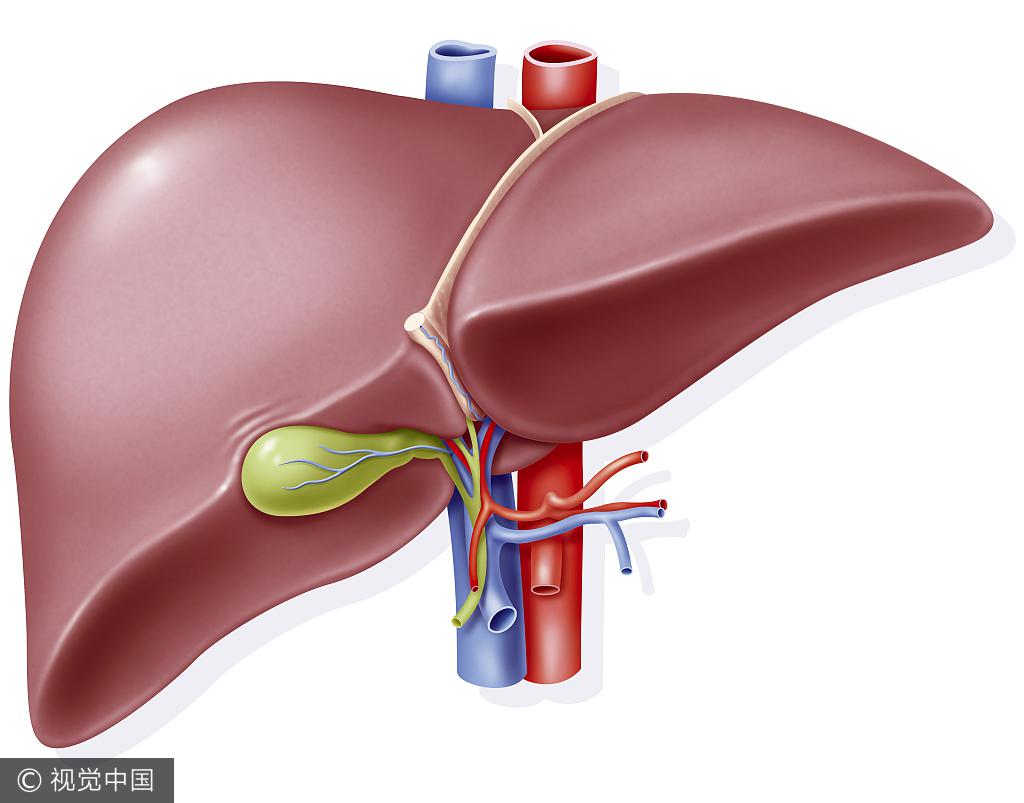

作為人體最大的消化腺,肝臟很容易受到病毒、藥物等各種病因的損傷,所以肝病的種類也很多。舉例來說,現在發病率最高的肝病實際上是脂肪肝,包括酒精性脂肪肝和非酒精性脂肪肝,脂肪肝的患病人數遠遠超過病毒性肝炎。

肝臟也被稱為“沉默的器官”,因為很多肝病是沒有明顯癥狀的,所以例行檢查非常重要。對于肝臟疾病,專科醫院可以開展很多檢查,但最最常用的就是肝功能和B超等常規檢查,一般我們體檢都會有的。